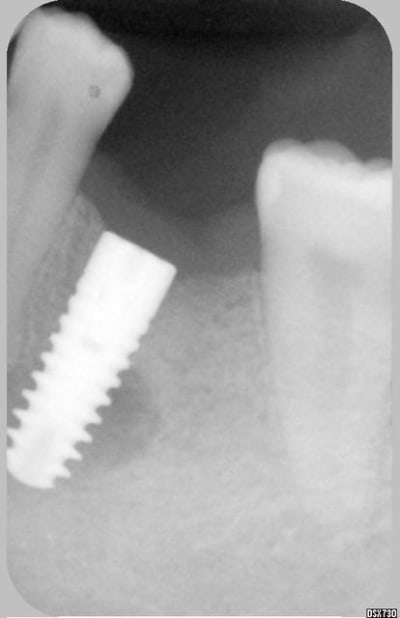

J'aimerai avoir votre avis sur ce cas (implant niveau 46).

L'image préop montrait déja une zone légèrement radioclaire.

celle-ci s'est "éclairci" sur le cliché à 3 mois, et est stable sur celui à 4 mois.

J'ai qd même posé aujourd'hui la vis de cicatrisation.

C'est complètement asymtômatique, trés stable, j'ai fait un essai de vissage d'un moignon à la clé dynamo et aucune douleur n'a été perçue.

Que faire ? attendre encore? poser la céram?